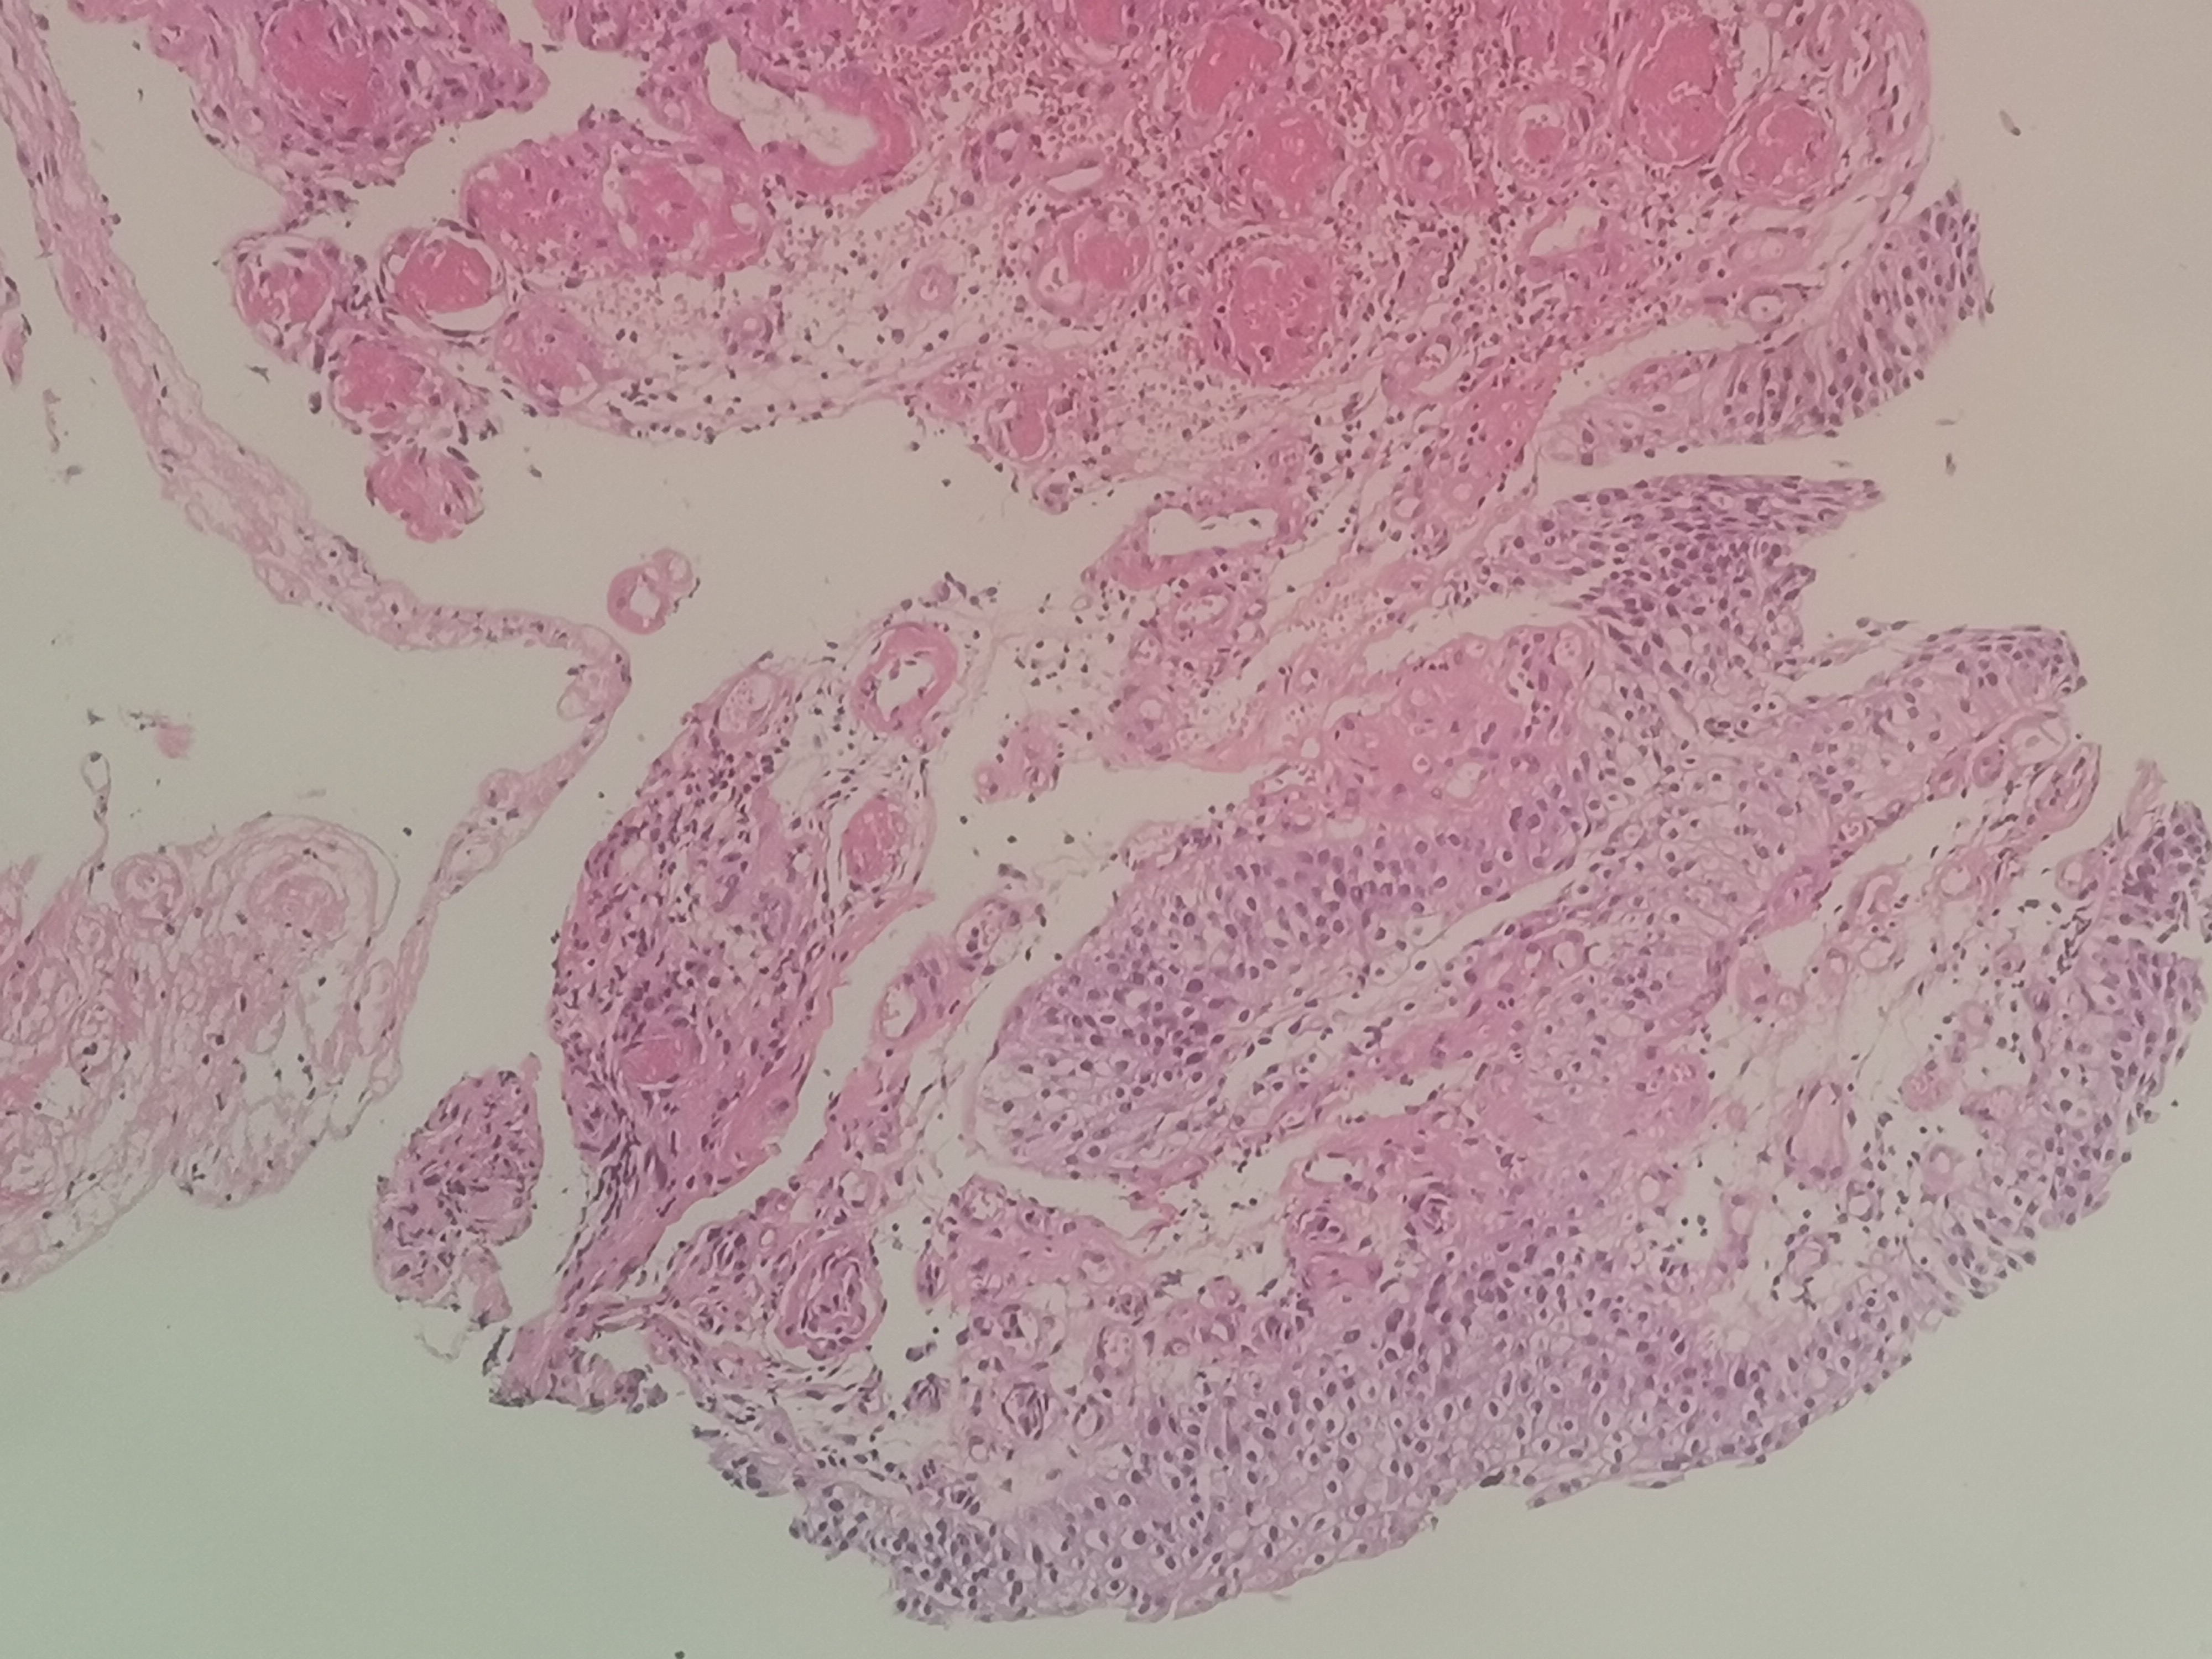

性别

男

年龄

80岁

临床诊断

膀胱肿物

一般病史

双输尿管结石,治疗中发现膀胱肿物

标本名称

大体所见

0.2x0.1x0.1厘米~0.3x0.15x0.15厘米3块。

患者1月前有急性尿潴留,急性肾衰,留置导尿下管,无其他病史和临床症状

建议:CK7;PAX2;PAX8;P504S等,排除肾源性化生!

尿路上皮反应性增生。